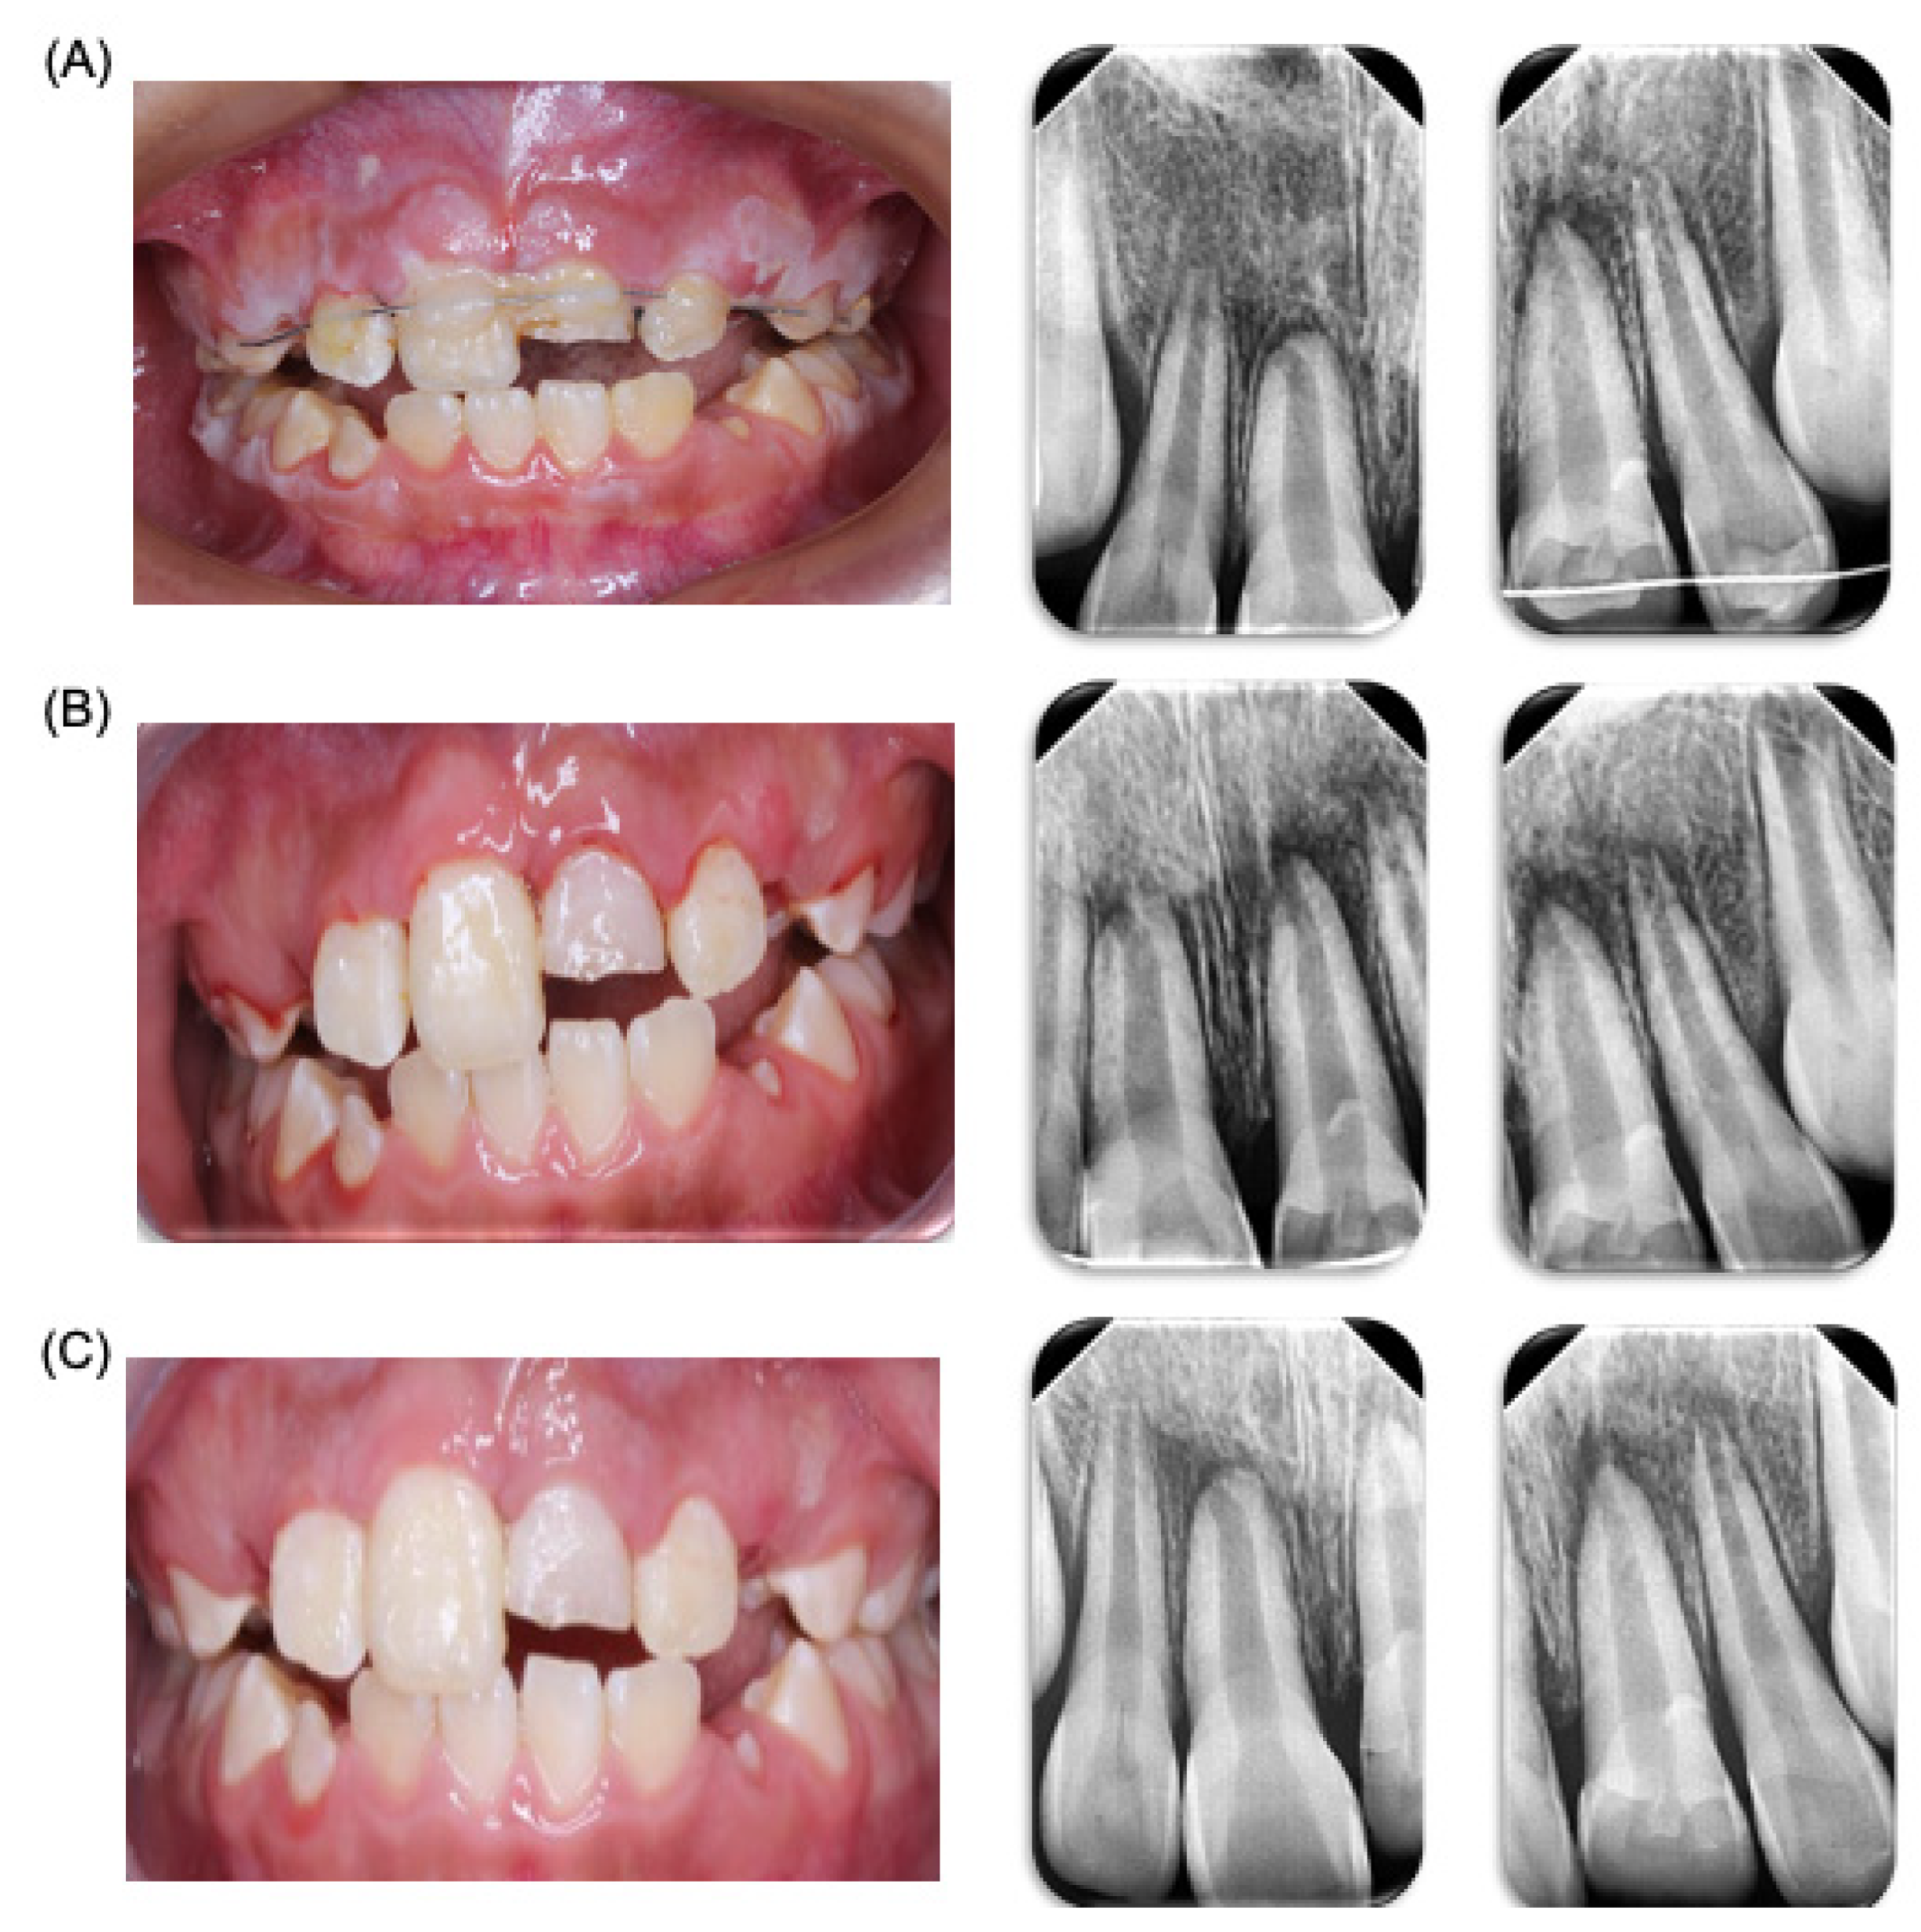

Three months later, the patient was referred to a specialist in esthetics, cosmetics, restorative, and implant dentistry (clinic of prothesis, specializing in esthetics, cosmetics, and restorative and implant dentistry, Faculty of Dentistry, Autonomous University of San Luis Potosi, SLP, Mexico). A direct resin restoration for tooth 21 was performed using a guide and stratification technique with prior waxing (Figure 4). Two weeks later, the patient visited the pediatric dentistry clinic for the placement of a custom sports guard, with follow-up appointments scheduled weekly. A month later, prophylaxis treatment and topical fluoride application were administered. In the subsequent months, a lingual arch and a Nance button were installed to maintain space, with ongoing control appointments. After a month and a half, both the lingual arch and the Nance button were removed (Figure 4), Currently, nine months post accident, the patient continues to be monitored by both pediatric dentists and endodontics, and is currently showing a positive prognosis; however, it will be necessary to evaluate at patient for long time in order be sure of success in treatment.

Figure 4.

Oral rehabilitation. Treatment of oral rehabilitation of patient. (A) Restauration protocol carried out. (B) Clinical revision at 7 months after accident. (C) Placement of the personalized sports guard. (D) Space maintainers placed in the patient’s mouth.